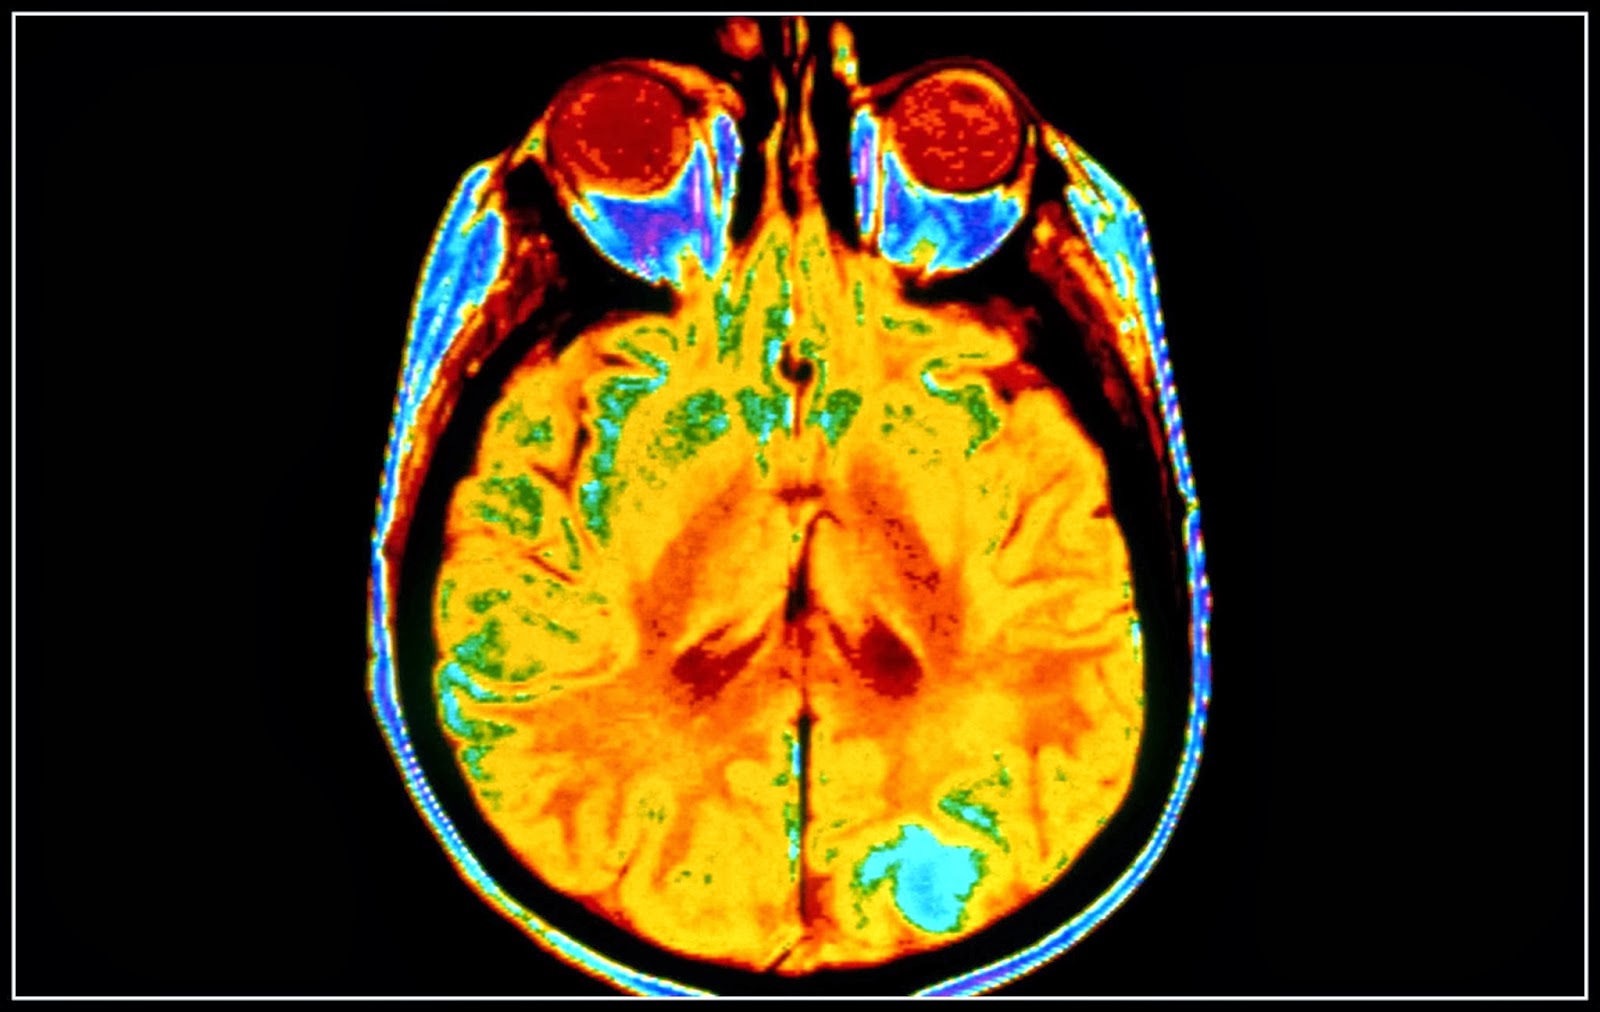

Όταν κλινικά πιθανολογείται η ενδοκράνια υπέρταση, οι ασθενείς θα πρέπει να υποβάλλονται επειγόντως

σε ακτινολογική απεικόνιση με υπολογιστική τομογραφία (CΤ) χωρίς

σκιαγραφικό. Ευρήματα που είναι υποστηρικτικά της ενδοκράνιας υπέρτασης

περιλαμβάνουν το εγκεφαλικό οίδημα, τη συμπίεση των βασικών δεξαμενών,

τον υδροκέφαλο, τα πιεστικά φαινόμενα ή τη μετατόπιση της μέσης γραμμής.

Ωστόσο, η απουσία αυτών των ευρημάτων δεν αποκλείει την ανάπτυξη

αύξησης της ICP στην πορεία.

Η μαγνητική τομογραφία (MRI) παρέχει μια πιο ακριβή αξιολόγηση του

εγκεφαλικού περιεχομένου σε ύδωρ ή των υποκείμενων καταστάσεων. Ωστόσο,

γενικά δεν είναι αναγκαία σε ασθενείς με υποψία ενδοκράνιας υπέρτασης

και μπορεί να είναι και επικίνδυνη, λόγω του μεγάλου χρόνου που

απαιτείται για την εξέταση και της ανάγκης παραμονής του ασθενούς σε

ύπτια θέση, η οποία μπορεί να επιδεινώσει την ICP.